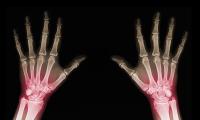

Vi har denne aften inviteret læge og ph.d. Louise Marianne Parke fra Reumatologisk Afdeling på Frederiksberg Hospital. Louise vil gennemgå psoriasisgigt, herunder sygdommens karakter og behandlingsmuligheder. Der bliver mulighed for at stille spørgsmål undervejs.

Foredraget varer ca. 45 minutter. Louise har desuden erfaring med psoriasis fra Dermatologisk Afdeling på Odense Universitetshospital (OUH).